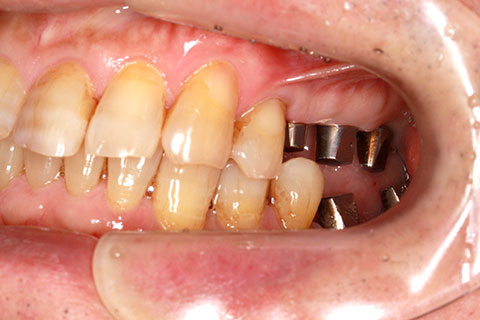

症例2

治療前

インプラント埋入時

治療後

- 年齢・性別

- 57歳男性

- 治療期間

- 3ヶ月

- 抜歯

- なし

- 治療費

- 154万円

- 備考

- 左上5.6.7 及び左下6.7欠損

- 治療内容

- 左上5.6.7と左下6.7欠損部にインプラント埋入

- 施術の副作用(リスク)

- オペによる知覚障害。インプラントによる歯肉炎。インプラント脱落。